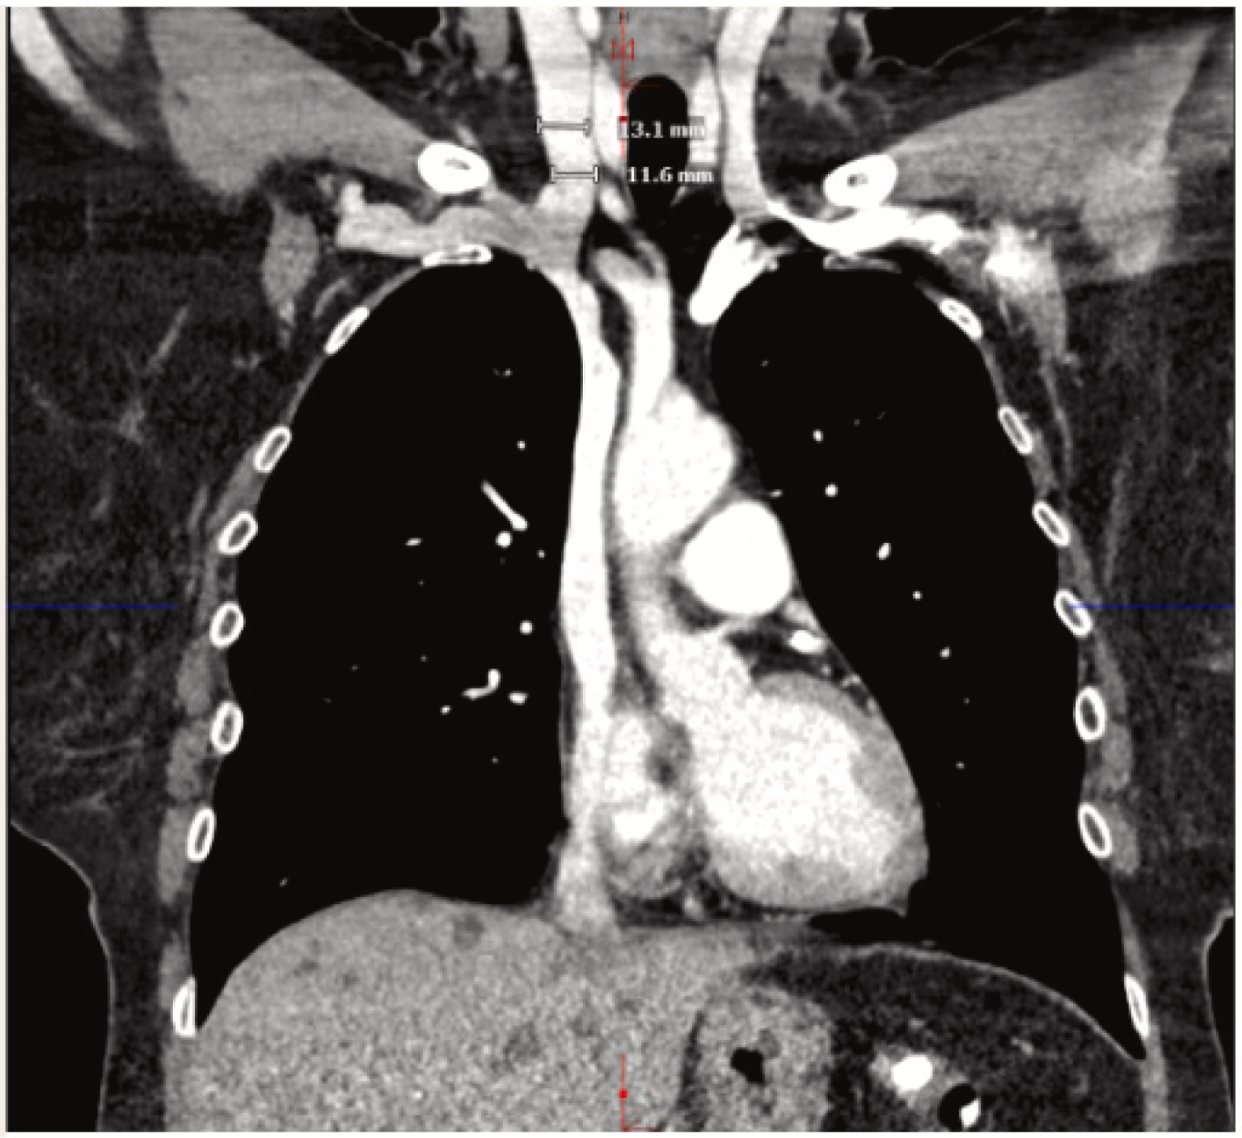

· 患者完成术前放射学成像检查(图1),并成功通过右侧颈内静脉路径植入AVEIR™ DR双腔无导线起搏器(图2),手术过程无任何并发症发生。

图1 右侧颈内静脉穿刺路径术前成像检查

· 患者术前静脉造影显示,因长期透析治疗,股静脉呈蜿蜒条索状,扩张尝试失败,故无法选择股静脉路径,最终计划通过上腔静脉路径植入双腔无导线起搏器;在上腔静脉路径植入中,左侧颈内静脉通常为首选,因其与右心耳角度较平缓,导管偏转更少;但本例患者左侧颈内静脉存在化疗输液港,导致该路径难以实施;因此,该患者的解剖结构决定了右侧颈内静脉为唯一合适的穿刺路径;